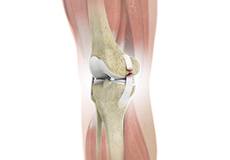

Total Knee Replacement

Total knee replacement, also called total knee arthroplasty, is a surgical procedure in which the worn out or damaged surfaces of the knee joint are removed and replaced with an artificial prosthesis.